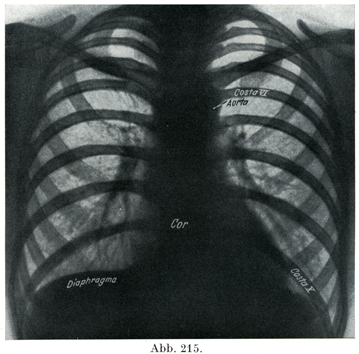

[図215]生体の肺 レントゲン像,血管が明かにみえる.